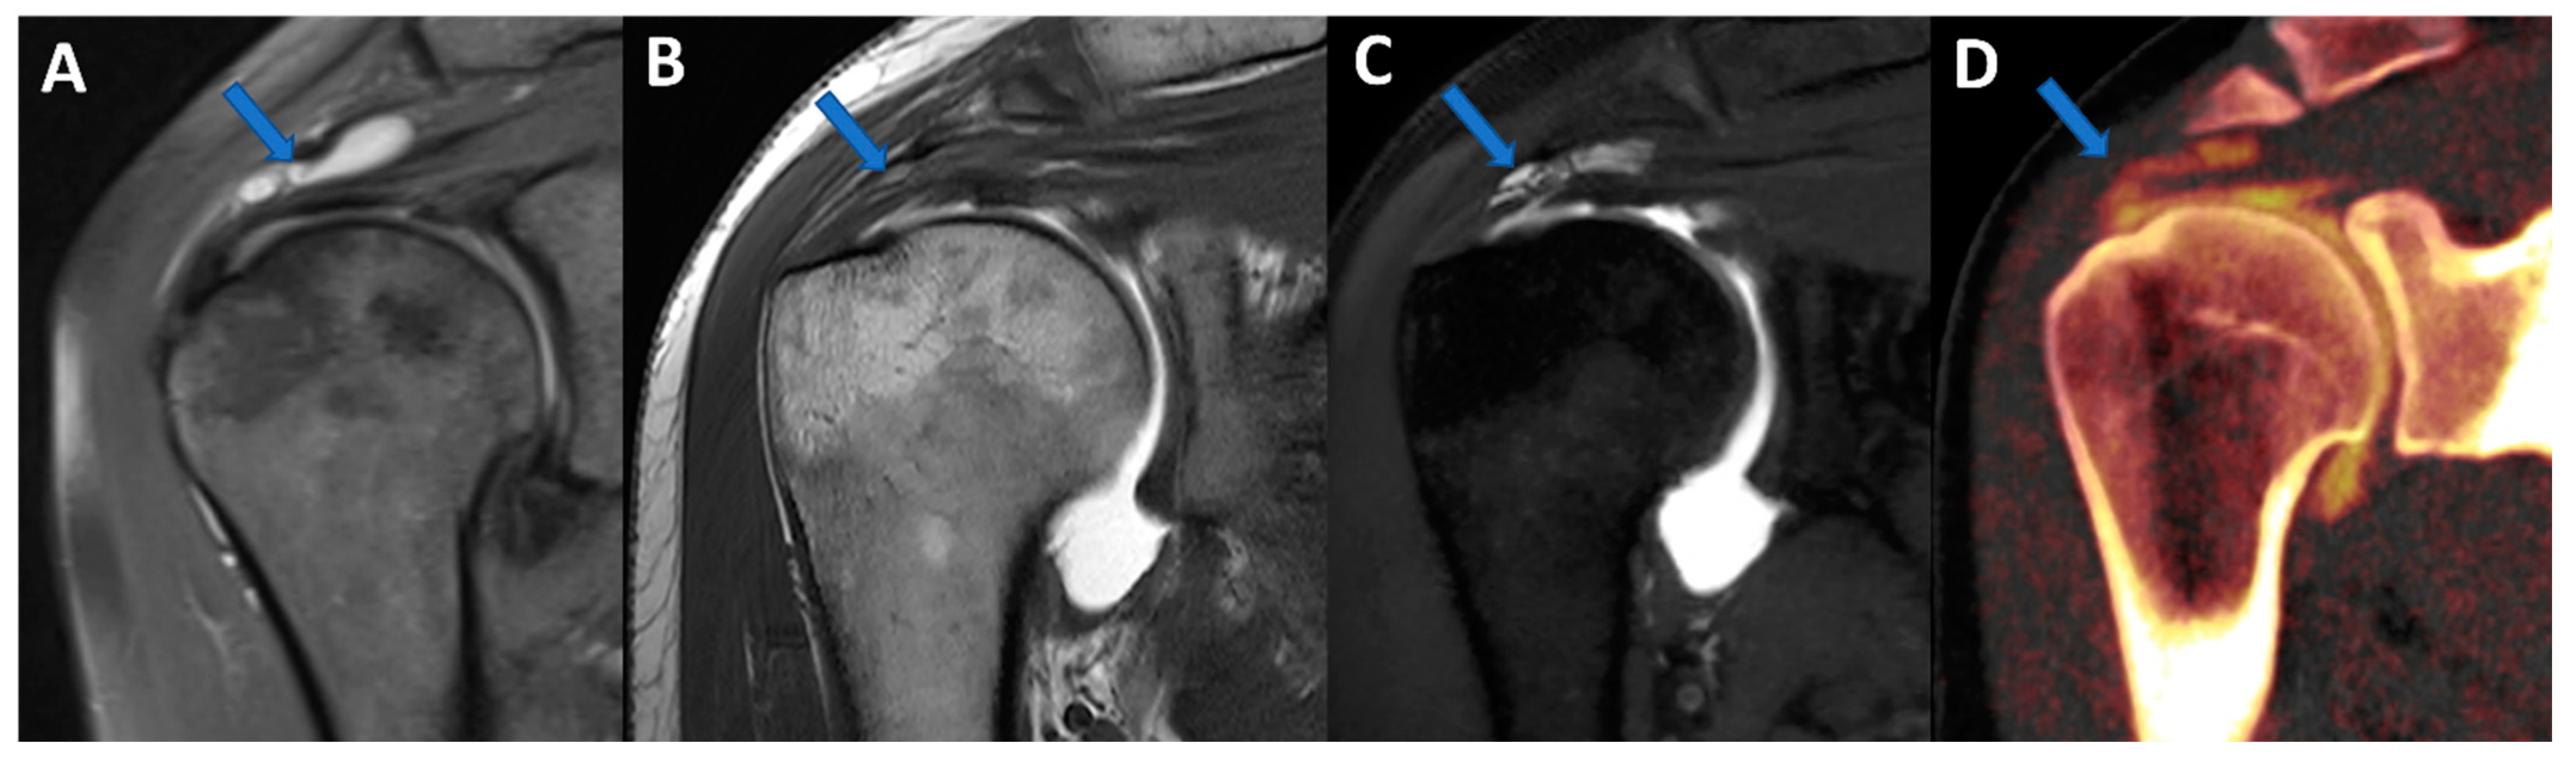

Figure 4.

Complete supraspinatus tendon diagnosed using DECTA. On the coronal standard STIR MRI image (A), a fluid collection located on the bursal side of the supraspinatus tendon can be identified (arrow). On the coronal T1 weighted TSE MRA image (B), the supraspinatus tendon appears irregularly thinned, as in a case of a partial tear. There is no apparent passage of contrast material on the bursal side (arrow). On the corresponding 1 mm PD fat-saturated image of the coronal plane (C), there are still no clear signs of complete tendon tears (arrow). The reconstructed DECTA 1 mm coronal image (iodine map; (D)) clearly demonstrates the presence of a complete tear with the passage of contrast material on the bursal side of the tendon (arrow).

Iodine maps have been largely employed in body and vascular imaging to increase the contrast among soft tissues because iodine maps enhance the signal coming from iodine contrast [20,21,22,23]. In a recently published paper [5], DECTA of the shoulder was superior in the detection of glenoid labrum and rotator cuff tears with respect to standard CTA (sensitivity rose from 84.2% to 92.1% for reader 1; specificity rose from 77.8% to 88.9% for reader 2). Conversely, intra-observer agreement was higher for CTA if compared to DECTA [24]. In clinical practice, iodine maps can be used to enhance the visualization of tiny, subtle tears by modulating the vividness of contrast material, with a subsequent increase in contrast within soft tissues, including articular cartilages (Figure 4). The possibility of modulating the signal from injected contrast material may be very useful in cases of difficulty injecting contrast material in the articular cavity. For example, the signal can be augmented in cases of diluted or small amounts of injected contrast material or in cases with pre-existing intra-articular fluid. Conversely, the signal from injected contrast material could be reduced in the case of poorly diluted contrast material, causing artifacts that may obscure the adjacent bony or soft tissue structures. Additionally, in clinical practice, the signal coming from contrast material can be changed depending on the radiologist’s choice of non-destructive flow.